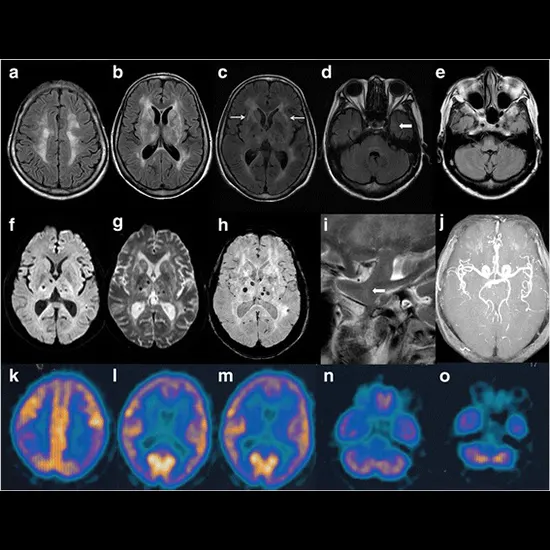

Fatal familial insomnia (FFI) is a rare and degenerative neurological disorder that affects the sleep-wake cycle and results in a wide range of symptoms, including insomnia, cognitive decline, and eventual death. FFI is inherited in an autosomal dominant manner, meaning that a person with a mutation in the responsible gene has a 50% chance of passing the condition on to their offspring.

The main hallmark of FFI is the progressive inability to sleep, which leads to severe insomnia that worsens over time. Other symptoms may include cognitive impairment, hallucinations, paranoia, weight loss, and autonomic dysfunction. As the disease progresses, patients may experience a complete inability to sleep, leading to a rapid decline in physical and mental health.

FFI is caused by a mutation in the PRNP gene, which leads to the accumulation of an abnormal form of the prion protein in the brain. Prions are misfolded proteins that can induce other normal proteins to adopt the abnormal conformation, leading to a cascade of pathological events in the brain.

MRI Brain with contrast 11500 5750

MRI Spectroscopy 8000 4000

Brain PET Scan 23900 11950